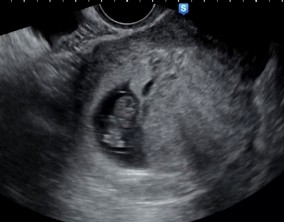

눈물로 실감한 아홉 번째 주

이경훈 원장님은 검사를 통해 나온 수치와 결과에 대해 자세히 설명해 주시고, 상황에 맞는 여러 방법을 함께 제시해 주셔서 큰 신뢰와 감사함을 느꼈습니다. 불안을 혼자 짊어지…